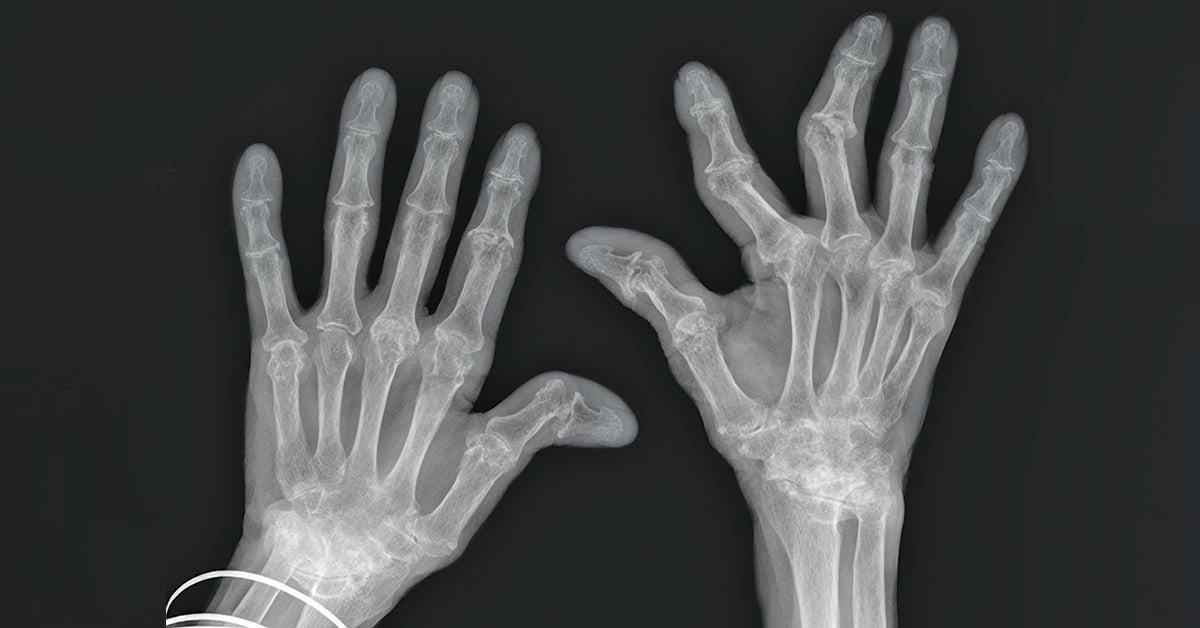

When you suspect a person may have an autoimmune disease that involves connective tissue, rheumatologists at Lehigh Valley Health Network (LVHN) are ready to help confirm the diagnosis and start appropriate therapies to slow and even halt disease progression. “We have the training and expertise to evaluate patients and get them on the correct treatment early on in their disease course. Early treatment typically leads to better long-term outcomes for our patients,” says rheumatologist Brian DelVecchio, DO, with LVPG Rheumatology. “We look at a patient’s history, physical exam, laboratory results and imaging to figure out what type of rheumatologic condition they have. Then, we get that patient treated correctly. It is also important in the treatment paradigm to match the intensity of the treatment to the severity of the disease.”